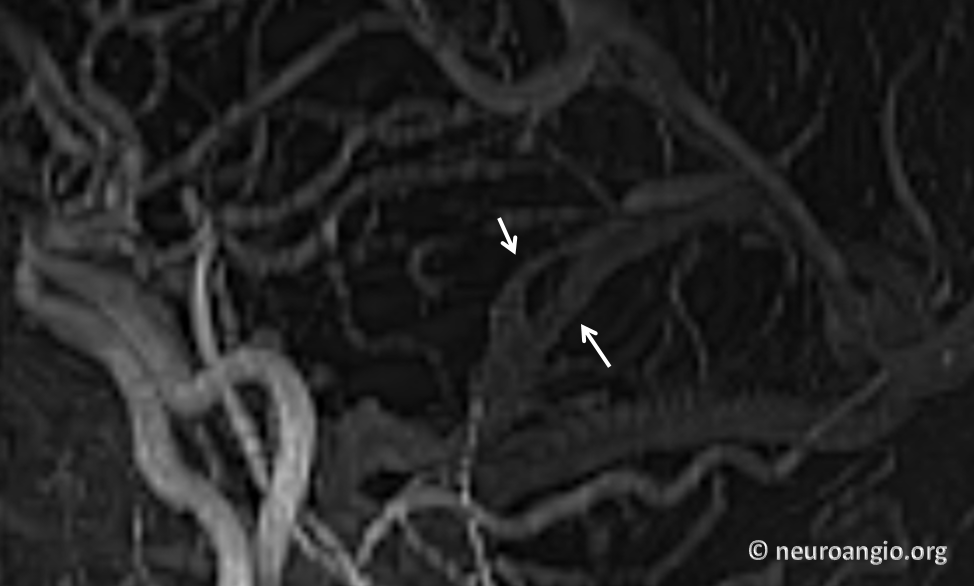

All of the above anatomic knowledge can become very useful in evaluation of venous thrombosis. Numerous collateral pathways develop in this setting attempting to compensate for the loss. The most dramatic cases usually involve the largest channel — the superior sagittal sinus. In this case, a man presented with what initially was thought to be vasculitis-related brain hemorrhage. Subsequent workup led to an angiogram, where sagittal sinus thrombosis with extensive trans-cerebral and trans-osseous emissary vein collateral channels was seen. In retrospect, these findings were present on the patient’s earlier contrast MRI. “Venovibe” or other contrast-enhanced MR venograms can very sensitive, particularly when interpreted with the appropriate index of suspicion. Noncontrast 2-D time of flight MRV I consider to be next to useless as a problem-solving technique. Any thin-slice postcontrast T1 study is vastly superior.